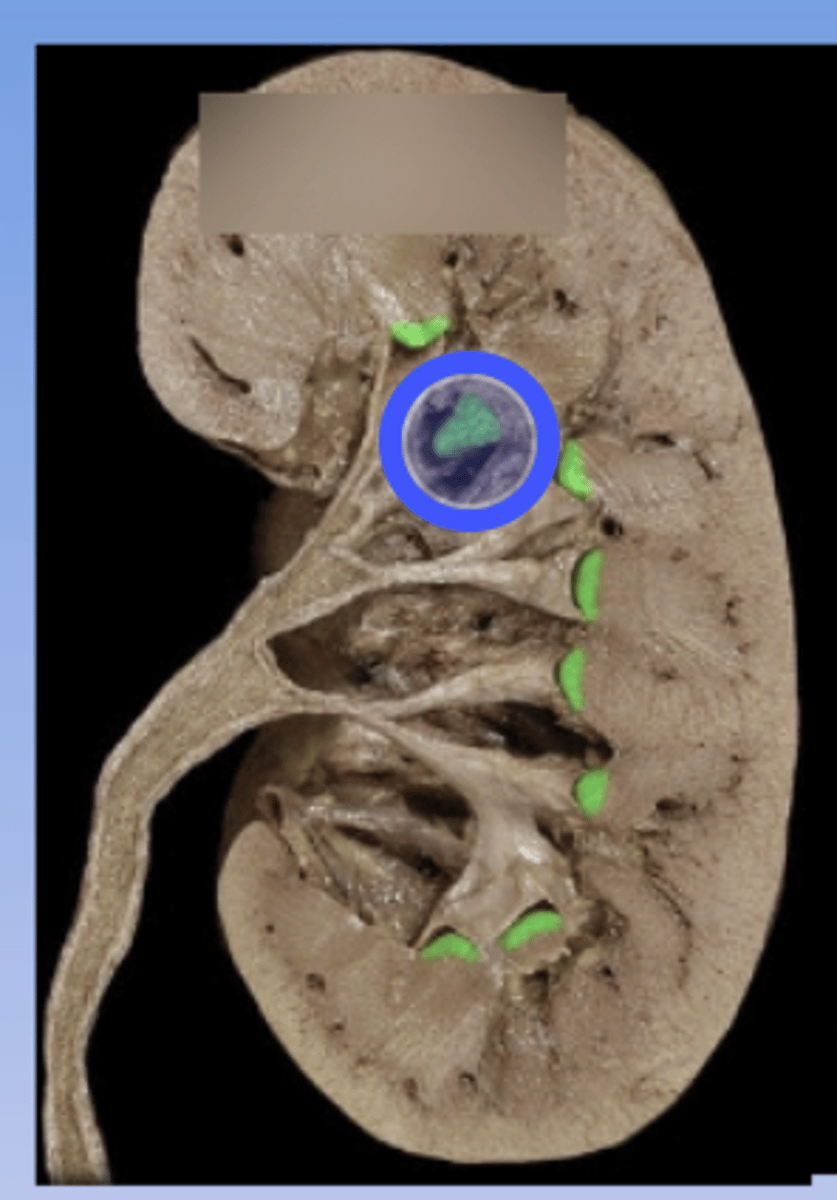

Papilla

Minor Calyx

Major Calyx

Renal Pelvis

Renal Hilum